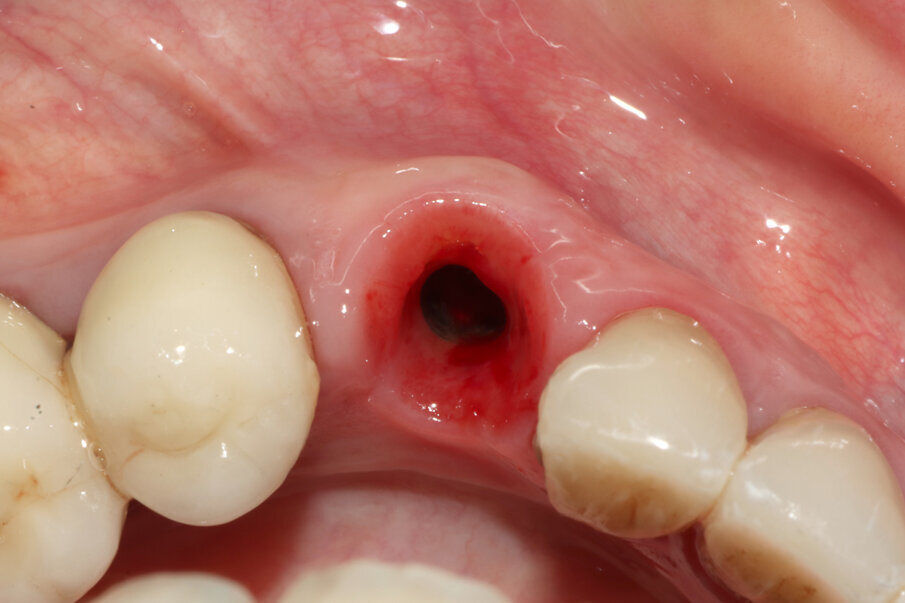

Figg. 9-11_Inserimento dell’impianto e costruzione di una corona provvisoria. Si noti la forma a “C” dello shield e, al termine dell’intervento, la compostezza dei tessuti, gestiti senza alcun tipo di lembo.